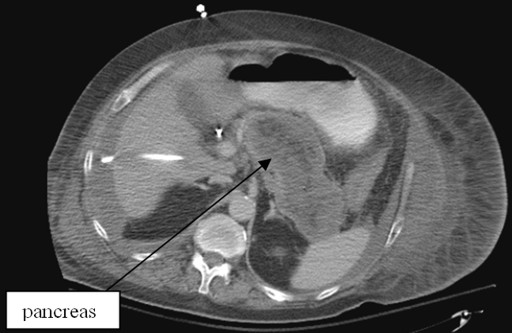

A 66-year-old Caucasian male was admitted with fever, malaise, generalized ill-defined abdominal discomfort and emesis. Past medical history was significant for diabetes mellitus, hypertension and coronary artery disease. The patient denied any history of hepatitis, pancreatitis or alcohol use. On examination, he was icteric with diffuse abdominal tenderness. Laboratory tests revealed leukocytosis (15,500 cells/mm3, reference range: 4,500-11,000 cells/mm3), ketosis, INR 2.2, creatinine 3.0 mg/dL (reference range: 0.7-1.2 mg/dL), abnormal liver enzymes (total bilirubin 9.1 mg/dL, reference range; 0.4-2.0 mg/dL; alkaline phosphatase 341 U/L, reference range; 38-126 U/L; AST 83 U/L, reference range; 12-42 U/L; ALT 40 U/L, reference range; 14-54 U/L), and normal triglycerides (106 mg/dL, reference range: 0-160 mg/dL). Serum amylase and lipase levels were 33 U/L (reference range: 36-128 U/L) and 15 U/L (reference range: 8-57 U/L), respectively. Ultrasound of the abdomen revealed a common bile duct diameter of 1.3 cm, cholelithiasis, ascites, an edematous pancreas and a diffusely echogenic liver. Abdominal CT scan with intravenous contrast confirmed the ultrasonographic findings showing ascites, diffuse pancreatitis and gallbladder distension with stones (Figure 1). Patient was hemodynamically unstable for surgical intervention. The hospital course was complicated by septic shock, worsening azotemia, and respiratory failure requiring fluids, vasopressors, broad-spectrum antibiotics, percutaneous cholecystostomy, mechanical ventilation and dialysis. The patient’s condition deteriorated over 3 weeks ending with his demise. Serum amylase and lipase levels throughout the hospitalization remained normal. Autopsy revealed severe acute necrotizing pancreatitis with centrilobular hemorrhagic necrosis of the liver and cholestasis.

Figure 1. CT scan of the abdomen with contrast (Case #1). |